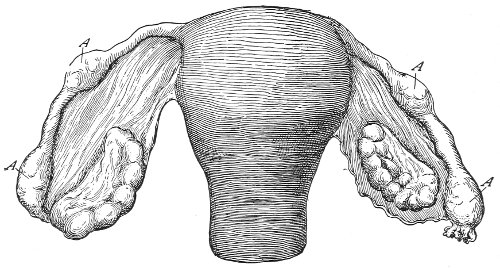

Cysts of the gland may be unilocular if formed at the expense of a single lobule of the gland, or multilocular if several lobules enter into their formation. These cysts may attain the size of the fetal head (Fig. 18).

Cysts of the gland or of the duct are formed by retention of the cyst-contents. The retention is due to occlusion of the duct, usually the result of inflammation. In some cases the duct remains pervious, and the retention is due to the altered character of the secretion of the gland, which becomes too viscous to pass, except under unusual pressure, along the duct.

These cysts contain clear yellow or chocolate-colored 42 fluid. The diagnosis of cyst of the vulvo-vaginal gland is usually not difficult. If we are in doubt in regard to the fluid character of the tumor, this may be determined with the exploring-needle.

Inguinal hernia, hydrocele of the canal of Nuck, cysts of the round ligament, and sacculated cysts of old hernial sacs may be mistaken for cysts of the vulvo-vaginal glands. In such cases, however, the tumor lies more in the upper and outer part of the labium majus, and extends to, and may be connected with, the external inguinal ring.

Cysts of the vulvo-vaginal glands should be treated by free incision and packing, or by extirpation. If the sac is emptied by the aspirator or by a small incision, it will refill. The best method is to extirpate the cyst. In case there has been no inflammatory action binding the cyst to surrounding structures, extirpation without rupture is easy. If rupture occurs, the cyst-wall may be dissected off with the knife or removed with the curved scissors. The wound may be immediately closed with deep and superficial sutures.